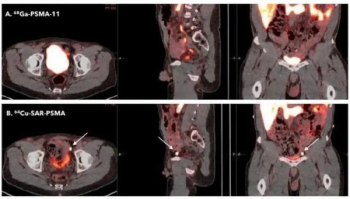

In addition to an August FDA fast track designation for PSMA PET imaging in patients with suspected metastasis, the radiopharmaceutical 64Cu-SAR-bisPSMA has earned another fast track designation for imaging of biochemical recurrence.